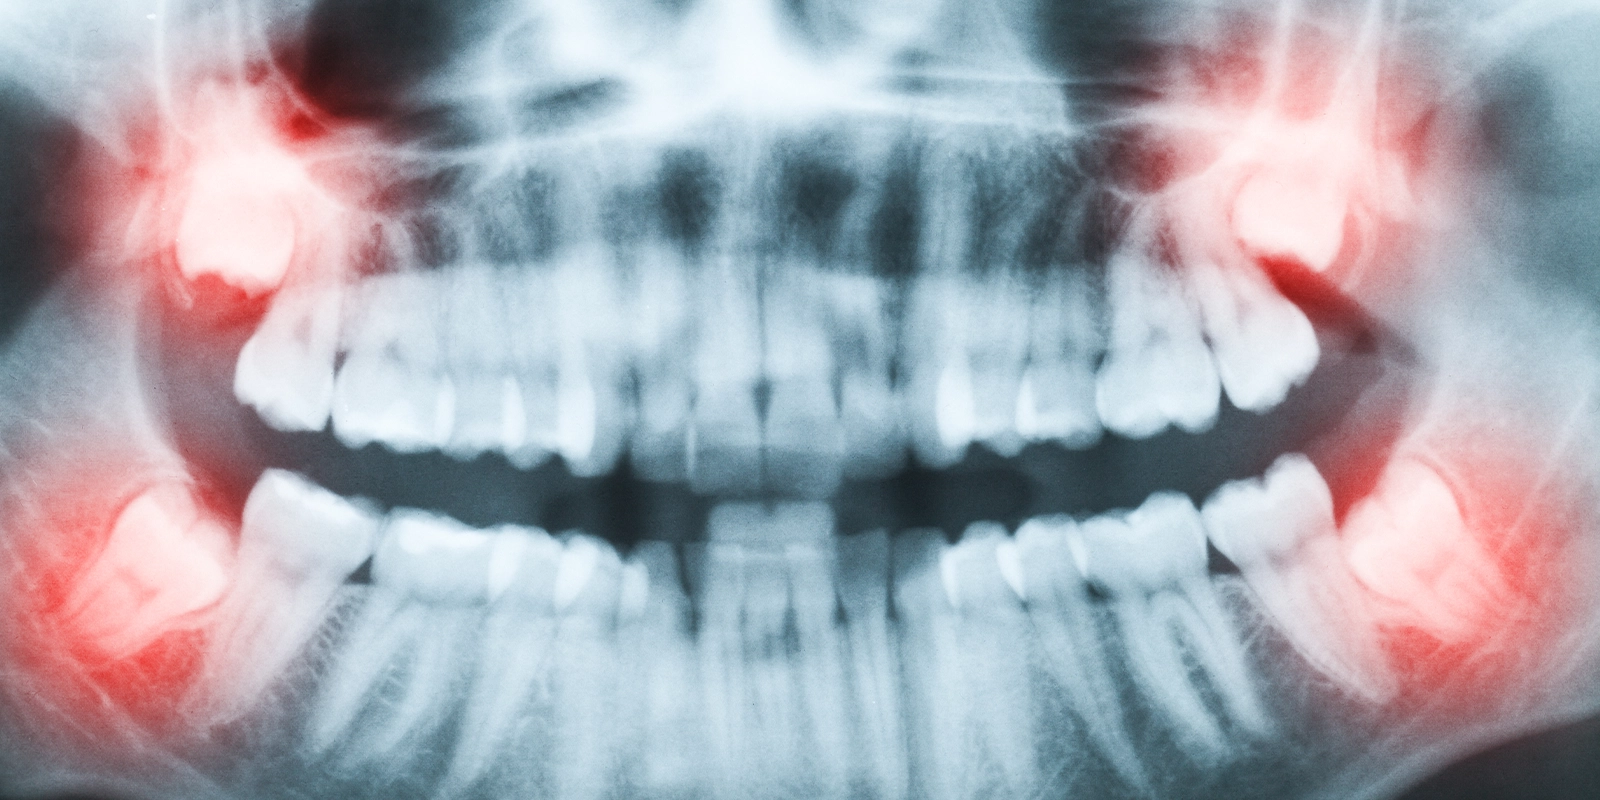

現代人は顎の骨格が小さくなる傾向があり、親知らずが正常に萌出するためのスペースが確保できないケースが増えています。このため、斜めに傾いたまま隣の歯に当たった状態で止まる「水平埋伏」や、歯茎の中に完全に埋まったままの「完全埋伏」の状態になることが珍しくありません。

また、親知らずの周囲に嚢胞(のうほう:液体が溜まった袋状の組織)が形成されていることが画像検査で確認された場合は、早期の対処が必要です。